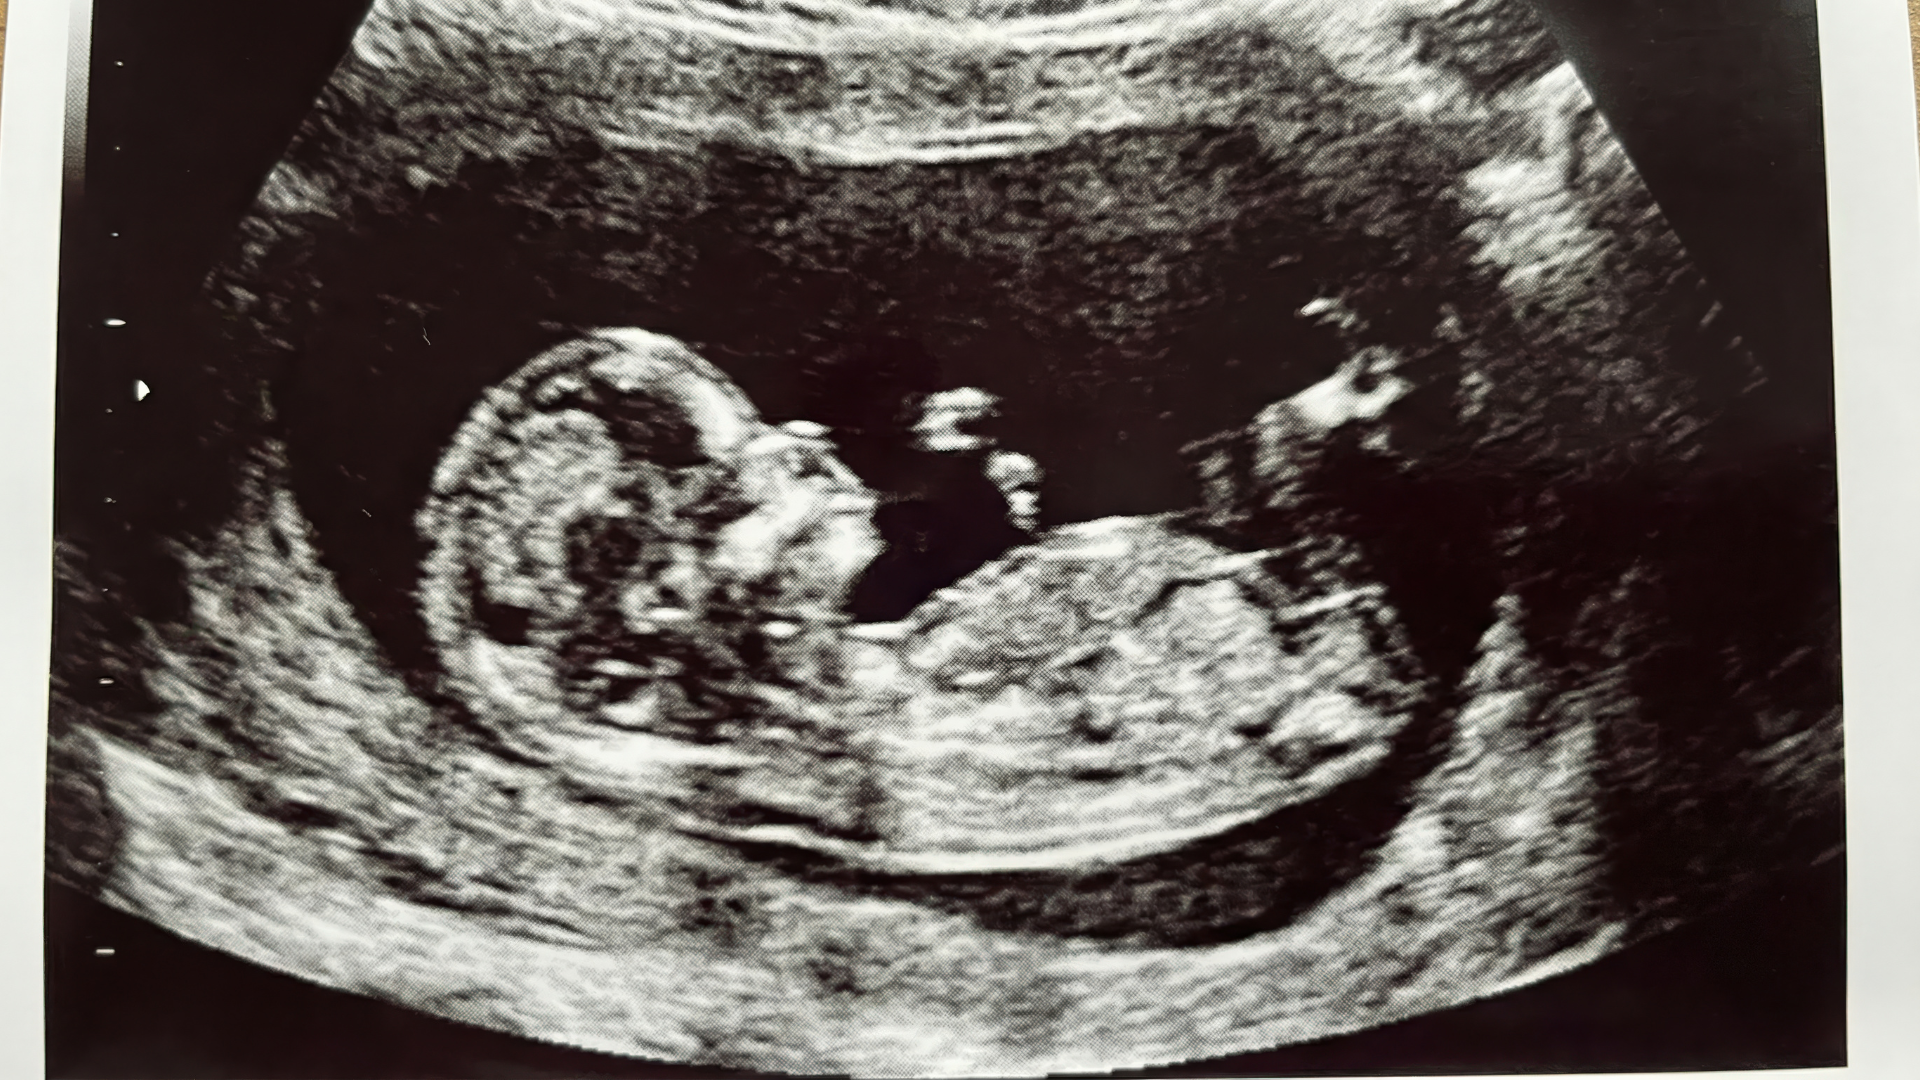

Siêu âm 2D, 3D, 4D khác nhau thế nào trong phát hiện hở hàm ếch?

- Siêu âm 2D: Là phương pháp cơ bản, giúp đánh giá hình thái chung nhưng hạn chế trong quan sát vòm miệng;